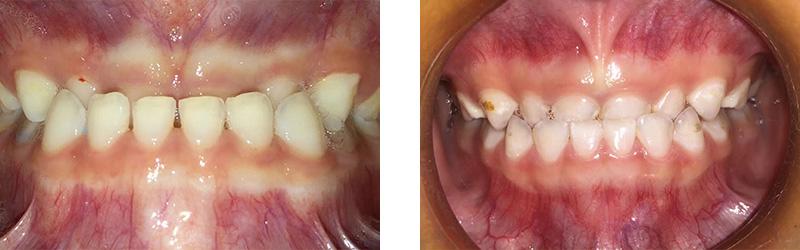

病例分享